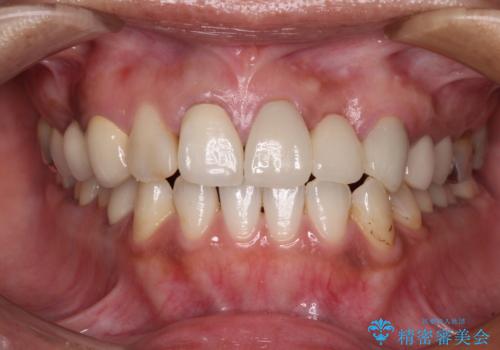

歯を削る量は増えますが、より長い期間再治療なく使用していただくことを最優先に考え、フルカバレッジのオールセラミックブリッジにて補綴することとしました。

我々としては、治療により状態が悪化することだけは避けたいと考えているため、歯全体を覆うクラウンにすることで、より長持ちする治療を提供いたしました。

外観はもちろんのこと、隙間なく安心して咬むことのできる前歯となり、患者様には大変満足していただきました。